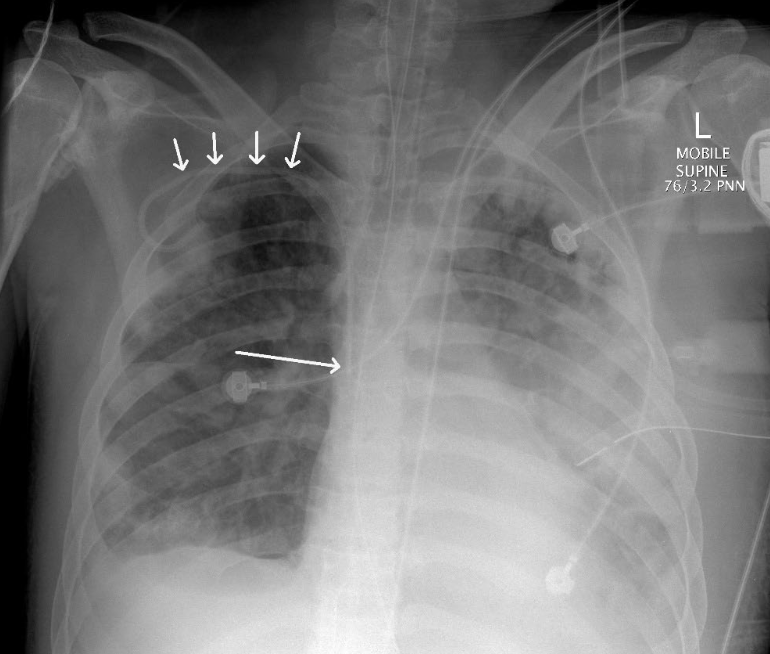

icc Ideal final position

To evacuate air – Most non-

dependant portion of the

lung

To evacuate fluid – Most

ETT

NGT

Central line

Right subclavian CVC

Vas Cath

ICC x 4